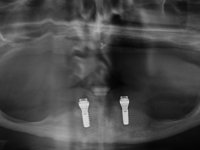

After clinical and radiological evaluation several rehabilitation plans were discussed with the patient. It was decided to extract the remaining lower teeth and do an overdenture retained by two dental implants with the locator attachement system to achieve a better retention and stabilization of the lower denture.

Two dental implants were planned in the CBCT scan, in the area of the inferior canines. The dental extractions were performed and, simultaneously, the alveolar crest was flattened and the implants were placed. Three issues were considered while implant placement: parallelism of the axis, same height of the implant’s neck, and same position in the coronal plan. This 3D insertion is essential to have a good retention of the overdenture in the future. Patient’s removable denture was fixed in the dental lab, to include the extracted teeth, and a soft-tissue relining was done over the healing abutments. After the osseo-integration period, a first impression was done with an open-tray and a doble-mix technique. This dental impression allowed the production of screwed wax-rims and an individual tray for a functional impression. A second impression, final, was done with an individual tray with a monophasic silicone. The occlusal wax-rims were correct in the mouth according to the full denture guidelines. Special care was taken with the occlusal vertical dimension and the support in the soft-tissues. A silicone bite registration material was used to better defined the intermaxillary relations. Teeth set-up was done in the dental lab with the selected tooth color. Due to the fact that the base was screwed to the dental implants, the teeth set-up was functionally evaluated in the mouth. Another silicone bite registration material was used to allow final occlusal adjustments. Finally, the locators were screwed and the retention nylons were selected according to the patient needs.